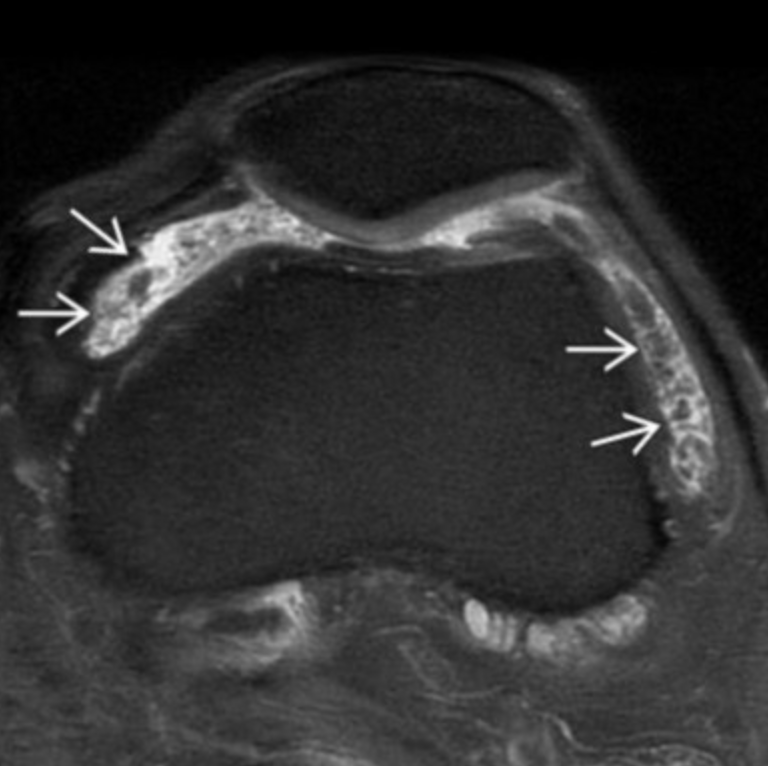

Synovial Osteochondromatosis

Primary (Reichel syndrome)

• Monoarticular (70% in knee)

• Seen in (relatively) younger patients (40-50s)

• Intra-articular bodies

• Many

• Uniform in size

• No joint degeneration

• Synovial hyperplasia commonly present

• Classically demonstrates blooming artifact on MR